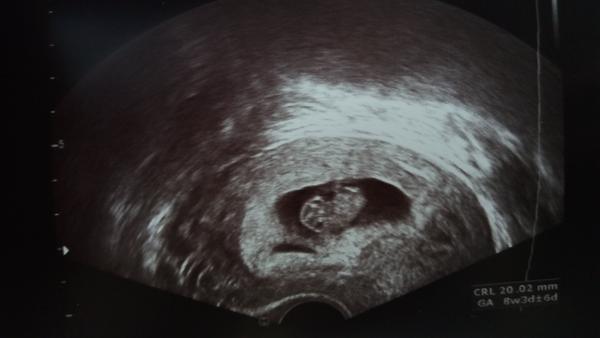

Krásný den všem 🙂 Pro mě je dneska opravdu krásný, protože jsem poprvé slyšela srdíčko svého miminka. Vše vypadá v pořádku a miminko krásně roste, už má 13 mm. Dnes jsem 7+2 a už mám i tehotenskou prukazku. Teď mě čekají velké odběry krve, to zas bude 😀

@monib66 povedená fotečka ❤️ Mám radost, že je vše v pořádku 🙏🏻🍀

@monib66 to je krásný snimecek, já tam mám vidět jen takovou malou zizalku 😀 ale jinak super že je vše v pořádku, určitě to tak půjde i dál 😉 kdy jdeš na další kontrolu? Já až za mesic